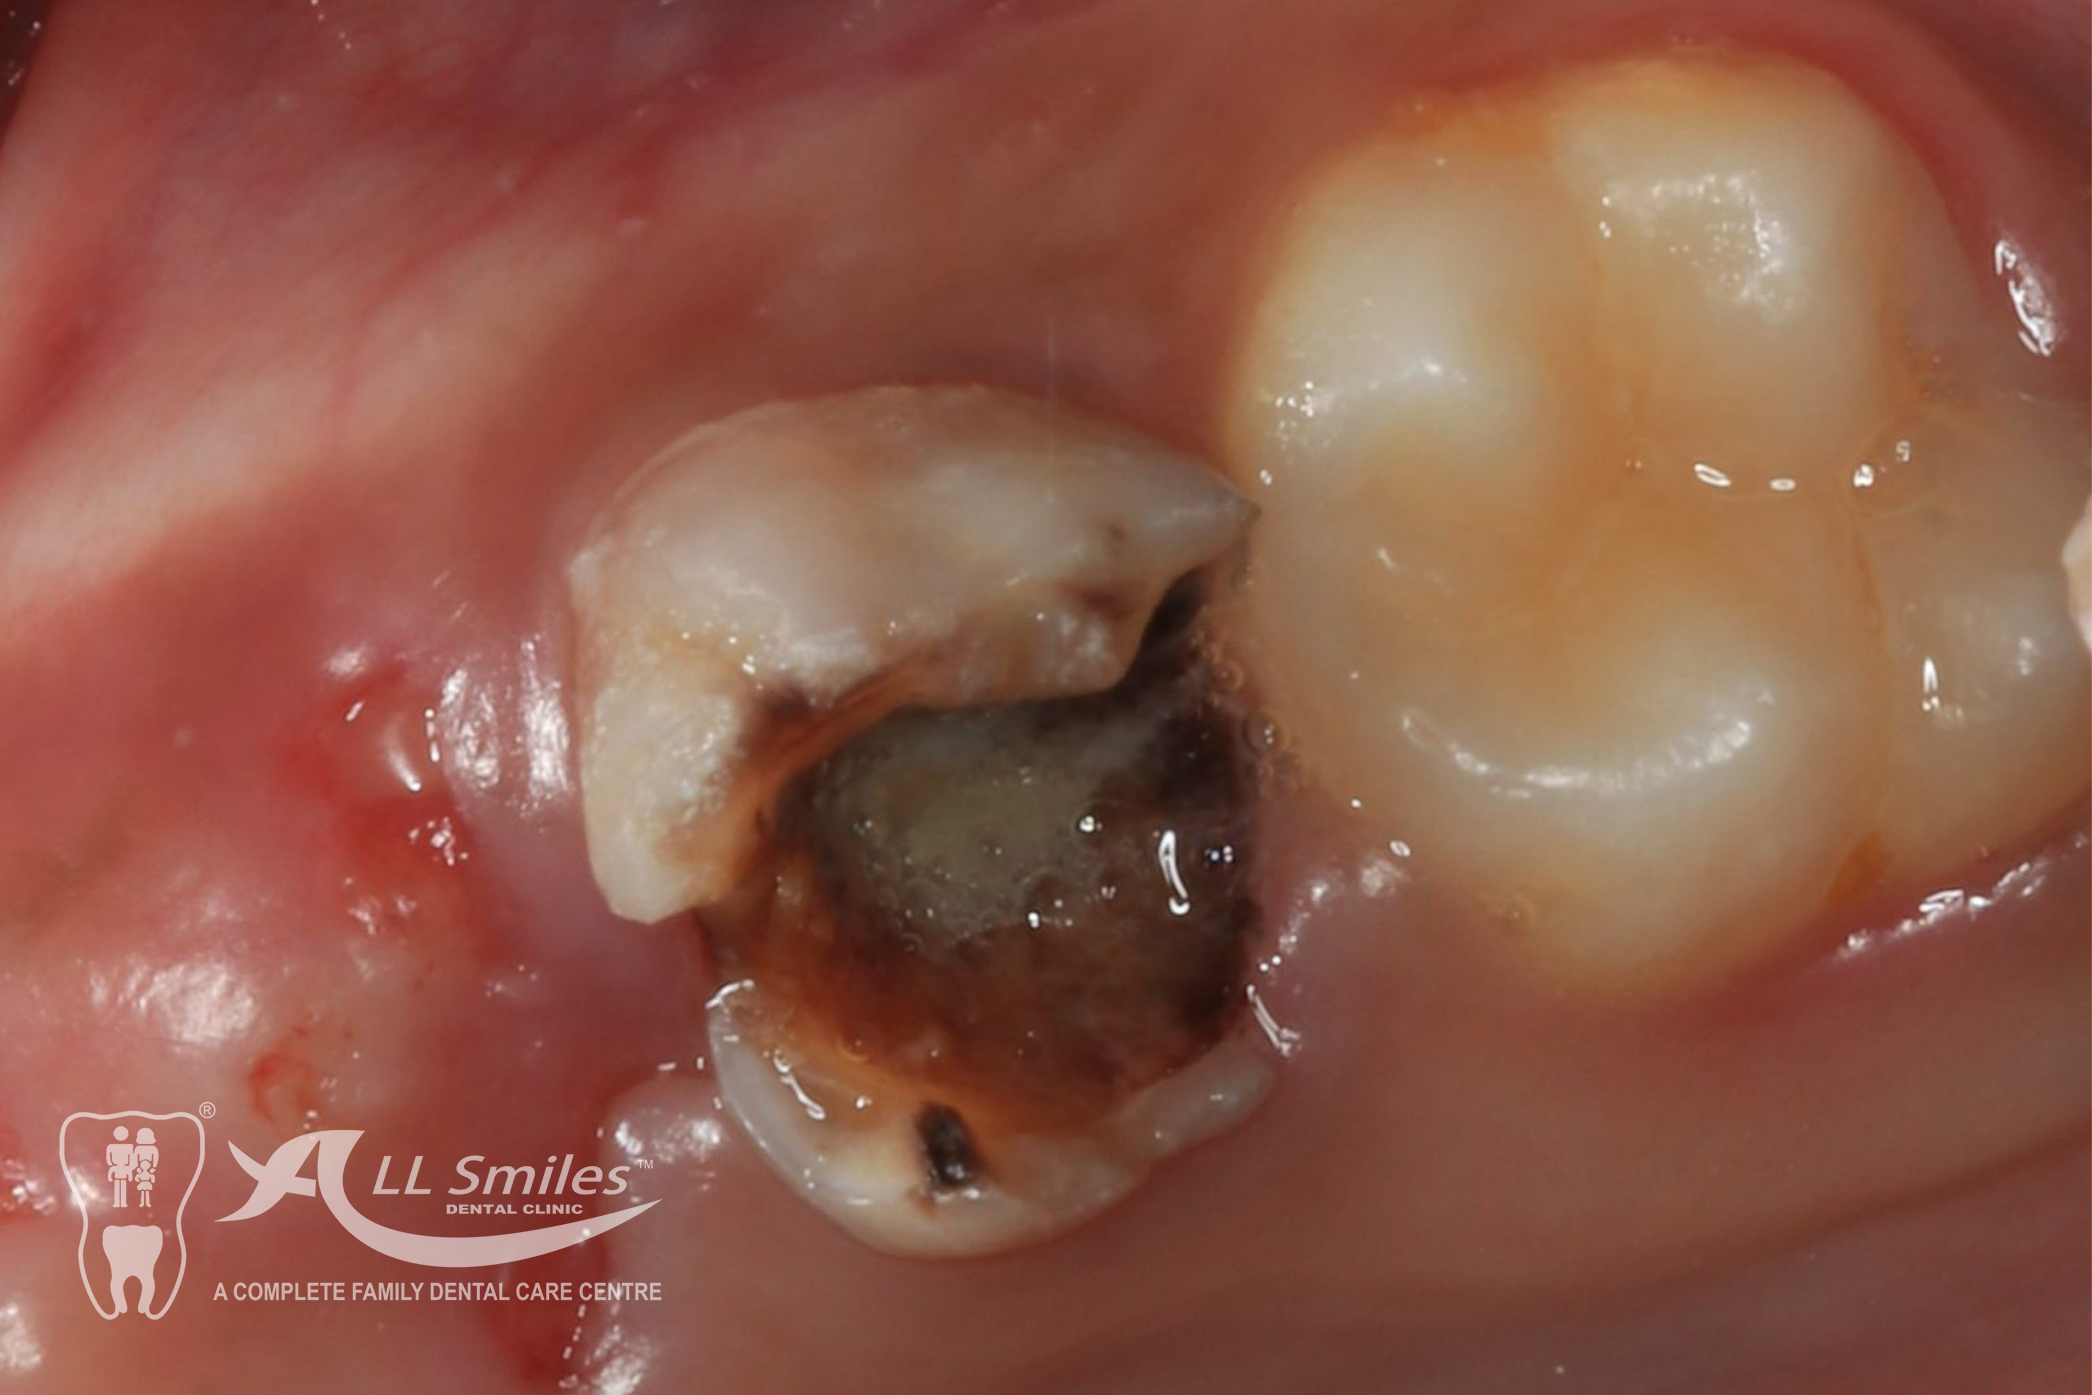

If a child has a cavity, the dentist will remove the decayed portion of the tooth and fill the space with a dental filling. Fillings can be made of various materials, such as composite resin or glass ionomer, depending on the specific needs of the child.

These are treatments performed on baby teeth to save them from extensive decay or infection.

Child Dentistry Gallery